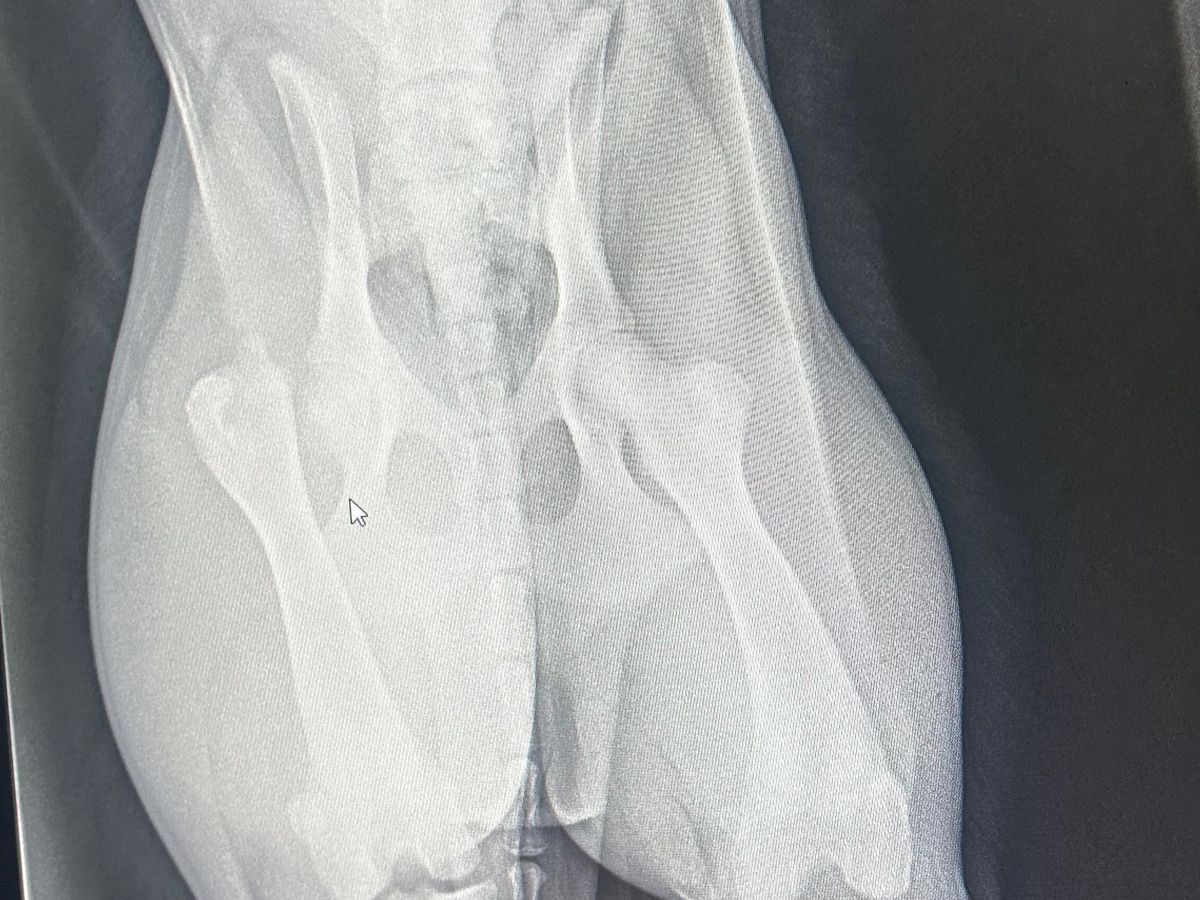

We have 2 puppies that we got back in October, and one of them, Sammie, got out and got into the road and was sadly run over by a truck. It could be a lot worse, but bless her heart, it broke her hip bone, and she's going to need surgery to fix it. She is in so much pain and it breaks my heart to see her hurting and feeling helpless. We have contacted a surgeon in Jonesboro, and they can do the surgery, but it's a lot more than I can do at this time. We appreciate any help. Thank you all so much!